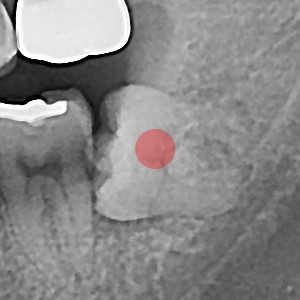

사랑니발치 20대/남성

ae27575af29d49719312fde5a1f0cca6_1764402576_9324.jpg